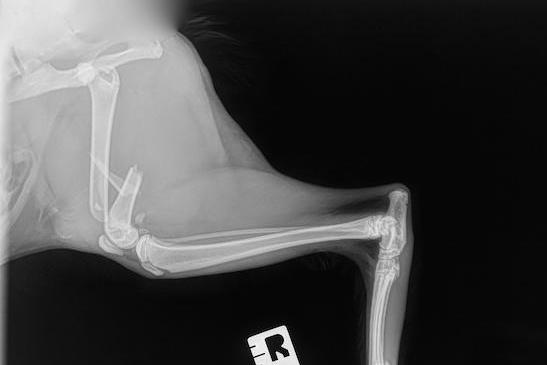

Les examens physique et orthopédique permettent d’orienter le diagnostic vers une fracture. En effet, une condition survenue subitement, particulièrement avec une histoire de trauma, peut mettre la puce à l’oreille. À l’examen, une boiterie marquée, une enflure importante, une instabilité, des crépitements et une douleur marquée lors de la palpation peuvent souvent être notés. La radiographie numérique consiste en la méthode de choix pour diagnostiquer cette condition. En effet, les os ont une opacité plus blanchâtre que les tissus mous sur la radiographie; cette méthode est donc efficace pour diagnostiquer les anomalies osseuses. Une discontinuité au niveau de l’os sur les clichés obtenus nous permet de poser un diagnostic de fracture. Étant donné que la radiographie consiste en une image superposée en 2 dimensions, plusieurs vues sont nécessaires pour être en capacité de reconstruire mentalement la fracture en 3 dimensions. Ainsi, un meilleur aperçu du nombre de fragments ainsi que du déplacement de l’os distal peut être obtenu avec un minimum de 2 radiographies. De l’air (noir sur la radiographie) au niveau des tissus mous peu suggérer une fracture ouverte, même lorsqu’aucune plaie n’est visible à l’examen orthopédique. Le CT Scan peut être indiqué lorsqu’un processus tumoral semble être à la base de la fracture. Il permet aussi de détecter de petits fragments que la radiographie peut manquer. Le CT Scan prend toute son indication lors de fracture avec de multiples fragments, bénéficiant ainsi d’une imagerie tridimensionnelle.